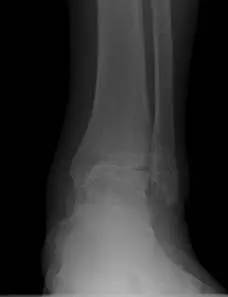

Ankle joint replacements are a reserved procedure for patients who meet certain criteria for functionality involving age, medical conditions, level of arthritis, and activity level, amongst others. The level of arthritis is typically severe and dibilitating as demonstrated in the x-ray image below. This person had a severe ankle fracture many years ago that was surgically repaired and later developed limiting arthritis to the point where they could no longer use their ankle because of pain. There is absence of joint space at the ankle joint along with remodeling of the bones around the ankle due to degeneration of the joint. The abnormal appearance of the thin bone called the fibula is a result of not fixing this bone when the patient had the original surgery.  This is referred to as malunion.

Pre and Post op Pics of Arthiitic Ankle S/P Total Ankle Replacement (TAR)

Preop, Intraop and Postop X-rays status post Total Ankle Replacement for Ankle Arthritis